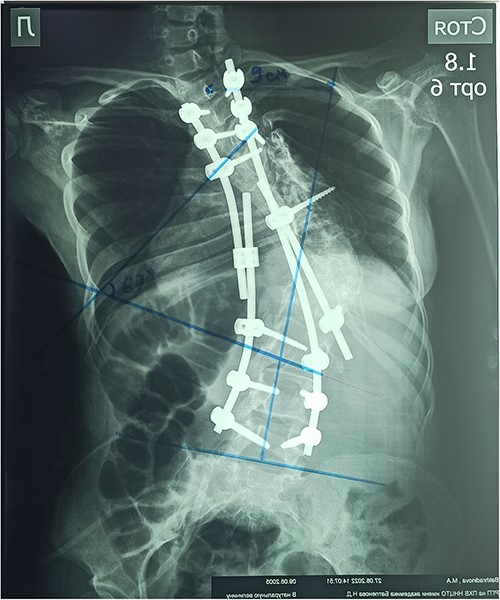

The patient underwent surgery: laminectomy of Th11, Th12, L1 vertebrae, partial excision of diastematomyelia, and decompression of the spinal cord; pedicular subtraction osteotomy at the level of Th9, Th10 vertebrae with resection of 11, and 12 ribs on the right side. Correction of congenital deformity and transpedicular stabilization (Medtronic, USA, no conflict interest) (Fig. 6).

In the early postoperative period, the patient complained of moderate local pain. There were no neurological disorders on the periphery of the lower extremities. The function of the pelvic organs was normal. On the seventh day after the operation, the patient underwent a X-ray control. After surgery, the Cobb angle was 67°, the correction was 60.9%, and the frontal balance was 9 cm (Fig. 7).